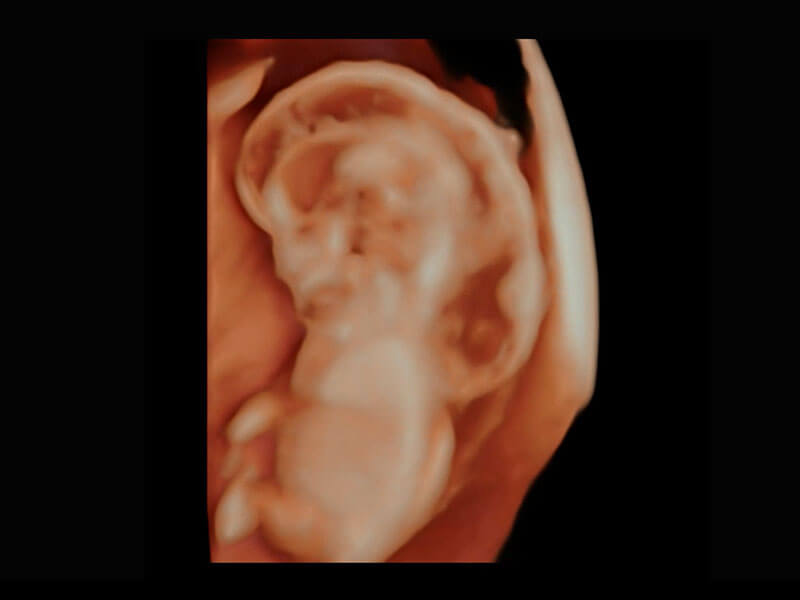

P60在胎儿早孕期超声筛查中为您带来优异的图像质量。

高分辨率容积成像-早孕胎儿